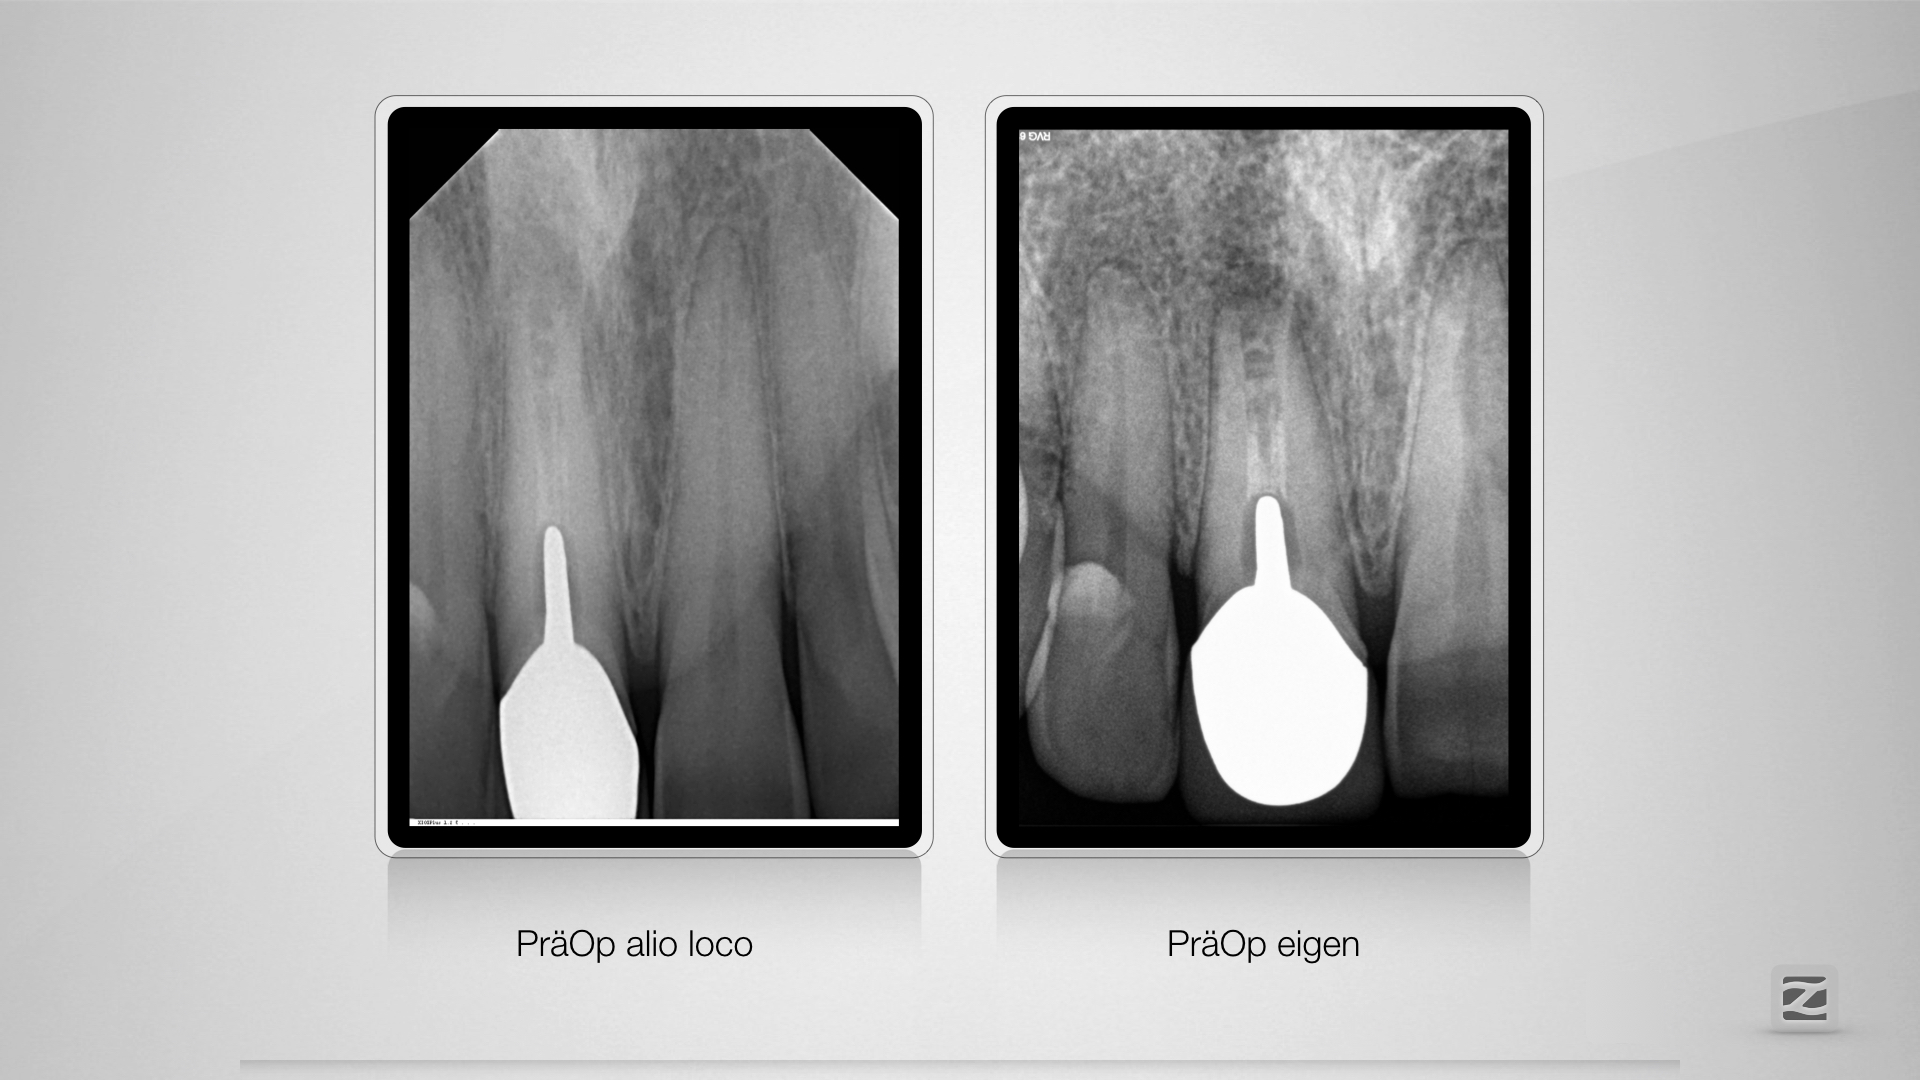

McFly! Jemand zuhause?